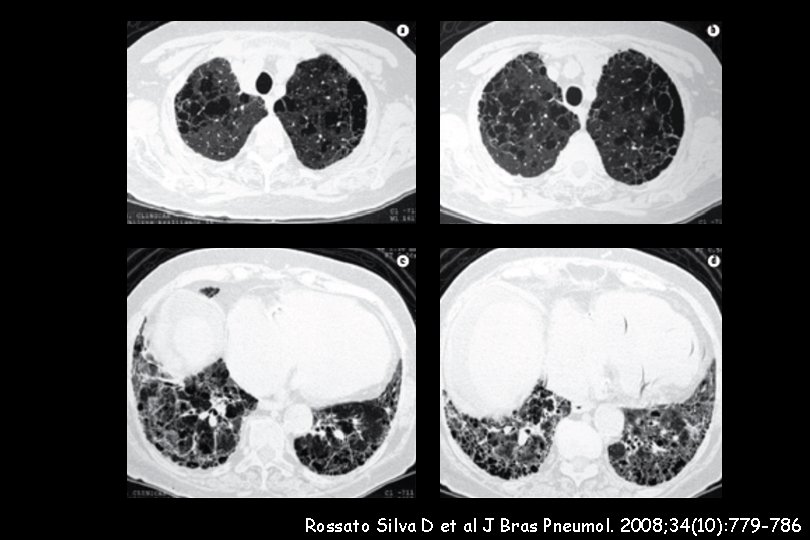

110 IPF patients wer evaluated. The prevalence of emphysema in the IPF cohort was 28% Pulmonary arterial hypertension (PAH) was evaluated with TTE and defined by an e. SPAP > 45 mm. Hg All IPF patients with emphysema showed PAH IPF with emphysema was highly associated with severe PAH (e. SPAP: 82. 3 ± 20. 2 mm. Hg versus 56. 7± 15. 3 mm. Hg, p < 0. 0001).

Rossato Silva D et al J Bras Pneumol. 2008; 34(10): 779 -786

e. SPAP (mm. Hg) 56. 7 ― 15. 3 e. SPAP (mm. Hg) 82. 3 ― 20. 2 Chest; Prepublished online February 18, 2009;